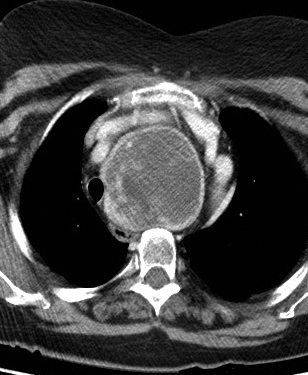

Retrosternal goitre CT axial